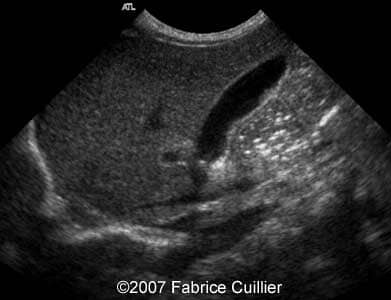

A 30-year-old patient, G3P2, was referred to our clinic at 36 weeks of gestational age after hyperechoic foci were seen in the fetal gallbladder on ultrasound. 13- and 22-week sonographic examinations were unremarkable. The 36-week ultrasound evaluation was normal except for an elongated echogenic mass seen in the gallbladder (Images 1A, 1B, 1C, 1D). Neither ascites nor hydrops were seen. The gallbladder appearance was identical on sonographic re-evaluation at 37 weeks GA (Images 3A, 3B). At 38 weeks of gestational age, a healthy female infant weighing 3200 g was born. There was no evidence of hematologic incompatibility, sepsis, or jaundice. Laboratory values including those for the cystic fibrosis gene, hemoglobinopathy, and liver functions were normal. On the fifth day of life, ultrasound was performed, showing a gallbladder of normal size containing several gallstones (Images 5A, 5B, 5C, 5D).

Images 1A, 1B. Transverse abdominal section at 36 weeks of gestational age through the fetal abdomen demonstrating a long, non-shadowing echogenic mass within the gallbladder.

1A

1B